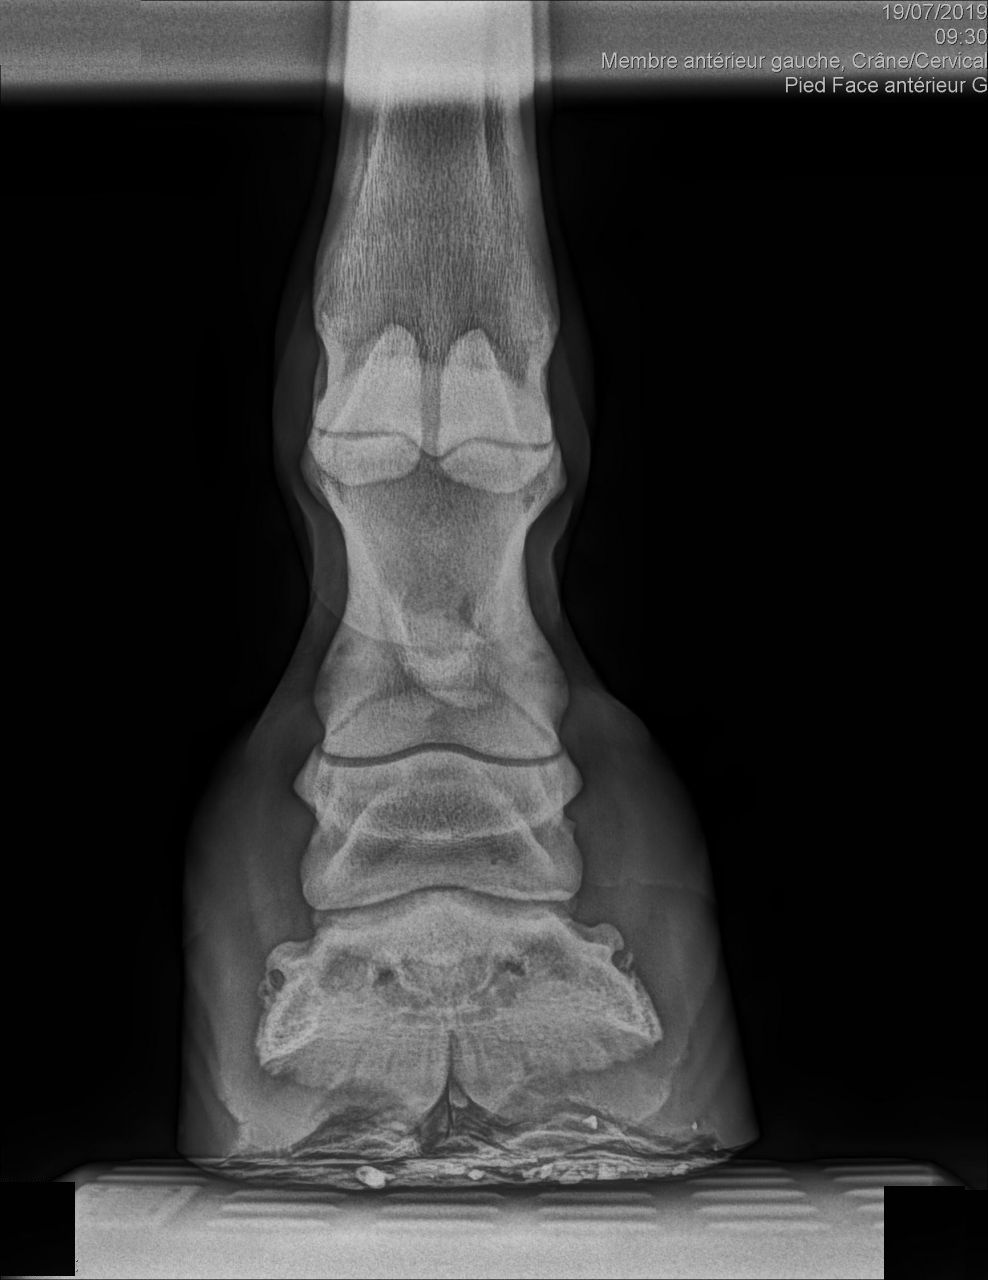

| Dire merci | Bonjour J'ai fait un bilan radio à ma mule qui est irreguliere pour recherche de la cause de sa sensibilité. Le veto m'envoie ce cliché de profil. C'est moi où on ne peut juger de l'épaisseur de la sole et que c'est le premier truc à regarder dans pareil cas ? Merci par avance pour vos avis éclairés... j'en ai d'autres de face et derrière si certains seraient capable d'évaluer la sole... Quand je demande au veto qui me parle absolument pas de pb de sole il me répond évasif "Ah oui peut être un peu fine" ![]() ![]() Édit: ajout photo de dos Message édité le 29/07/19 à 19:52 [edit modo suppression coordonnées véto] Ce message a été modifié par un modérateur. |

| Dire merci | Si : ras sauf légère demineralisation de P3 . Tester réaction aux AI Donc bon moi je veux bien hein mais la première chose à savoir et surtout si la seule anomalie est sur la phalange c'est est ce qu'elle est protégée convenablement... Non? J'espère avoir tort c'est pas mon métier mais je n'ai malheureusement pas assez confiance. Donc même si il se trompe sur le diag c'est pas tellement grave, mais je paye pas un photomaton qui me prend la moitié du visage. Donc c'est ma question ... cette radio est elle acceptable dans le cas d'une recherche d'explication pour pied sensible? |

| Dire merci | Franchement je lui demanderai de refaire le premier cliché qui n est pas du tout cadré on ne voit même pas le bas. Ou alors c est moi c est que sur mon téléphone ça ne s ouvre pas correctement |

| Dire merci | Même avis : on devrait voir un bout de la planche ! Comme sur l'autre cliché. Mon véto a limage en direct sur son ordi, ça arrive souvent que le 1er cadrage ne soit pas terrible : il recommence immédiatement sans me compter l'essai foireux. |

| Dire merci | Pareil, premier cliché inexploitable pour voir la sole correctement... |

| Dire merci | Disons que ça dépend ce qu'il voulait voir, s'il voulait les articulations c'est bon, s'il voulait une photo du pied c'est coupé c'est clair ! Mais je pense qu'il cherchait une photo des articulation, sur une photo de pied l'articulation du boulet est souvent coupée (cf radio de cody) Elle est bizarre d'ailleurs ta radio goss, on voit pas du tout la boîte cornée |

| Dire merci | zapi merci je pense que tu as raison! Il voulait prendre le boulet avec. En tt cas ça me paraît le plus probable et recevable argument. Je reste déçue de ne pas avoir un cliché de la sole mais pas de scandale à faire. |